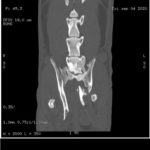

Gracias a vosotros por fin hemos podido realizar el TAC que necesitaba Allan. Os dejamos por aquí algunas de las imágenes y el primer informe emitido por el hospital.

Allan sigue ingresado y tendrá que estarlo varios días más, no sabemos aún cuántos. Deben estabilizarlo y observarlo antes de valorar si es conveniente operarlo. El estado del tórax sigue siendo delicado y tienen que controlar el encharcamiento que tiene en un pulmón. El TAC ha mostrado, además de nuevas fracturas, fracturas anteriores. Es decir, Allan no sólo está así porque recientemente haya recibido un golpe, sino que tiene signos de haber recibido al menos otro golpe anteriormente que también le produjo fracturas, unas fracturas que “se han soldado como han podido”. Como no tenemos ninguna información de Allan hasta la pasada semana que fue cuando recibimos el aviso, no sabemos si antes era capaz de caminar o de hacer caca él solito.